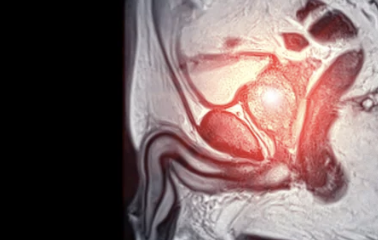

5. 조기 발견을 위한 검사와 진단

전립선암은 증상보다 정기검진으로 먼저 발견되는 경우가 많습니다.

특히 PSA(전립선 특이항원) 수치가 중요한 지표입니다.

검사 방법 설명 특징

| PSA 혈액검사 | 혈중 전립선 특이 단백질 측정 | 4ng/mL 이상이면 추가 검사 필요 |

| 직장수지검사(DRE) | 손가락으로 전립선 크기·단단함 확인 | 간단하지만 정확도 낮음 |

| 경직장 초음파 | 전립선 크기, 결절 유무 확인 | 비침습적 검사 |

| 조직검사 | 세포 채취 후 병리 분석 | 최종 확진 단계 |